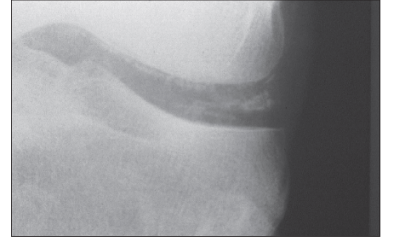

Considere a seguinte imagem:

Com base na imagem apresentada, assinale a alternativa correta sobre seu diagnóstico e/ou tratamento.